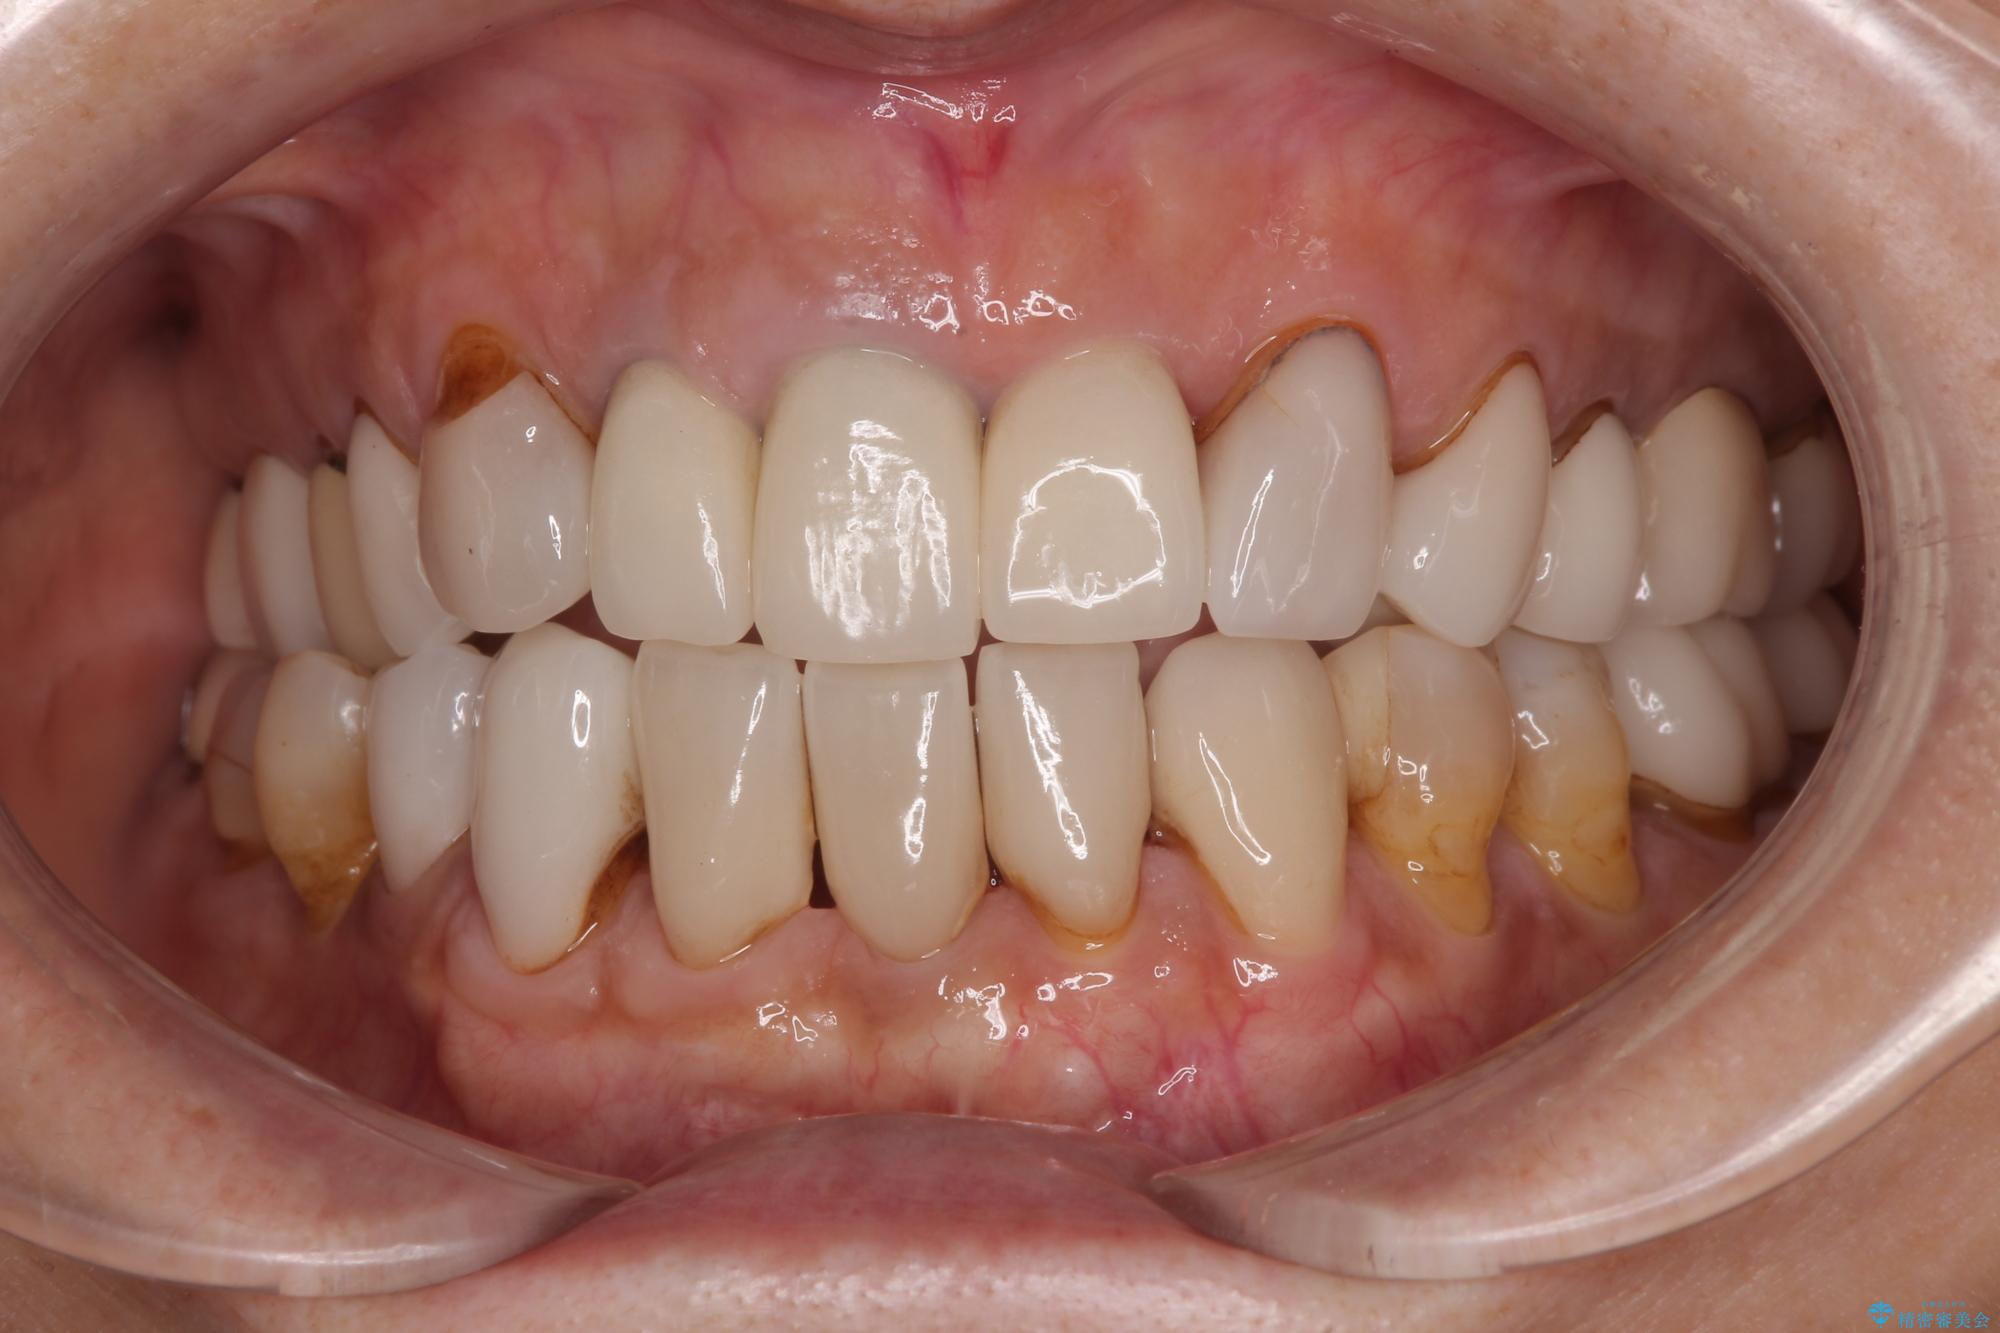

- 前歯のセラミックが欠けたり色調が不揃いであったりすることを気にして来院された患者様です。

色調が統一されるだけでなく、歯肉ラインに見えていた茶色の境目も綺麗に改善されました。